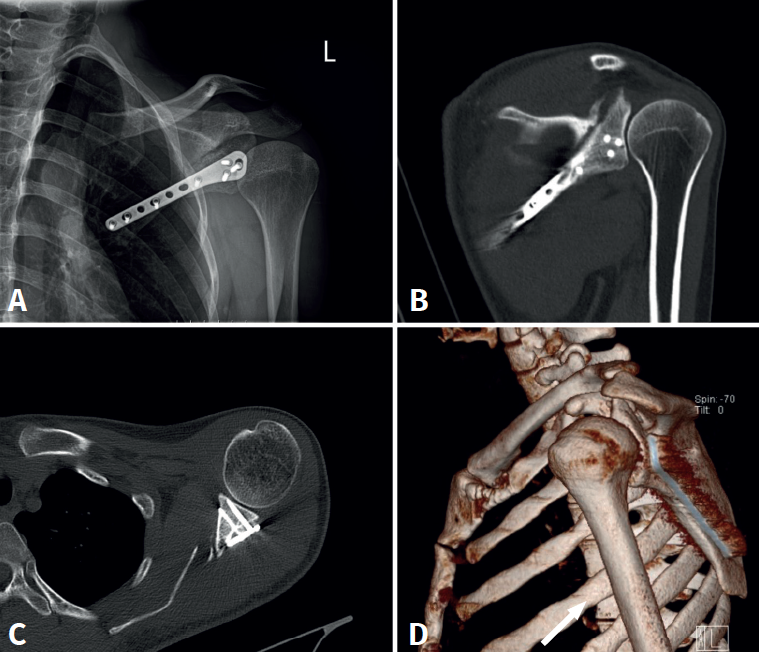

En el postoperatorio se realizan radiografías simples para comprobar la correcta reducción y síntesis de la fractura, y a los 2 meses se realiza una TC para controlar el proceso de consolidación y cerciorarse de que no existen tornillos intraarticulares (Figura 6).